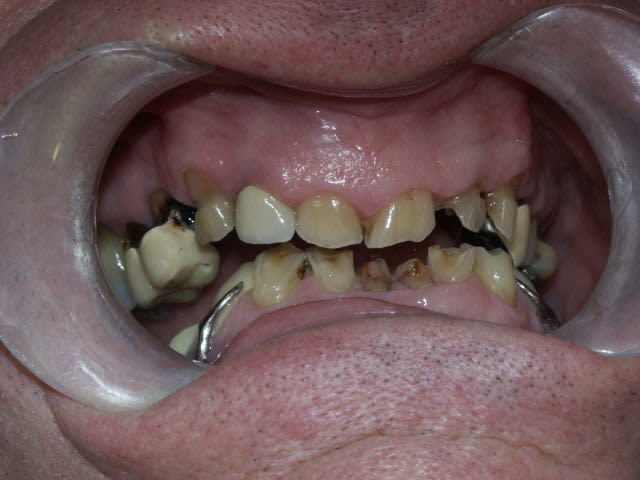

la suite...

Le constat est le suivant, corrigez-moi si je me trompe:

on a eu des extractions non compensées à la mandibule qui ont provoquées des égressions des dents maxillaires postérieures.

une abrasion +++ du bloc antérieure avec égression "physiologique" au fur et à mesure de l'usure.

On a ainsi un décalage important (comme une marche d'escalier) de la courbe d'occlusion (Spee) entre le secteur antérieur et postérieur.

La difficulté de la thérapeutique consistera à rattraper le mieux possible ce décalage pour avoir une courbe d'occlusion "harmonieuse".

Il conviendrait d'augmenter la DV partout mais on risque de se retrouver avec les difficultés suivantes:

- en postérieur, l'augmentation de DV sera importante et on risque de vite se retrouver avec des couronnes avec un rapport couronne / racine défavorable.

- en antérieur, le gain de DV obtenu sera plus faible du fait de l'égression physiologique des dents. Le dilemne est de savoir si cela permettra d'avoir assez de place pour faire des couronnes.

Pour gagner un peu de hauteur sur les dents antérieures pour les futures CCM, je pensais faire des gingivectomies. Les bruxos ont souvent un parodonte en béton avec de la GA à revendre, favorable à cette technique. Cela permettrait de limiter l'augmentation de DV. Le seul truc qui coince c'est que le patient n'a pas des racines très longues.